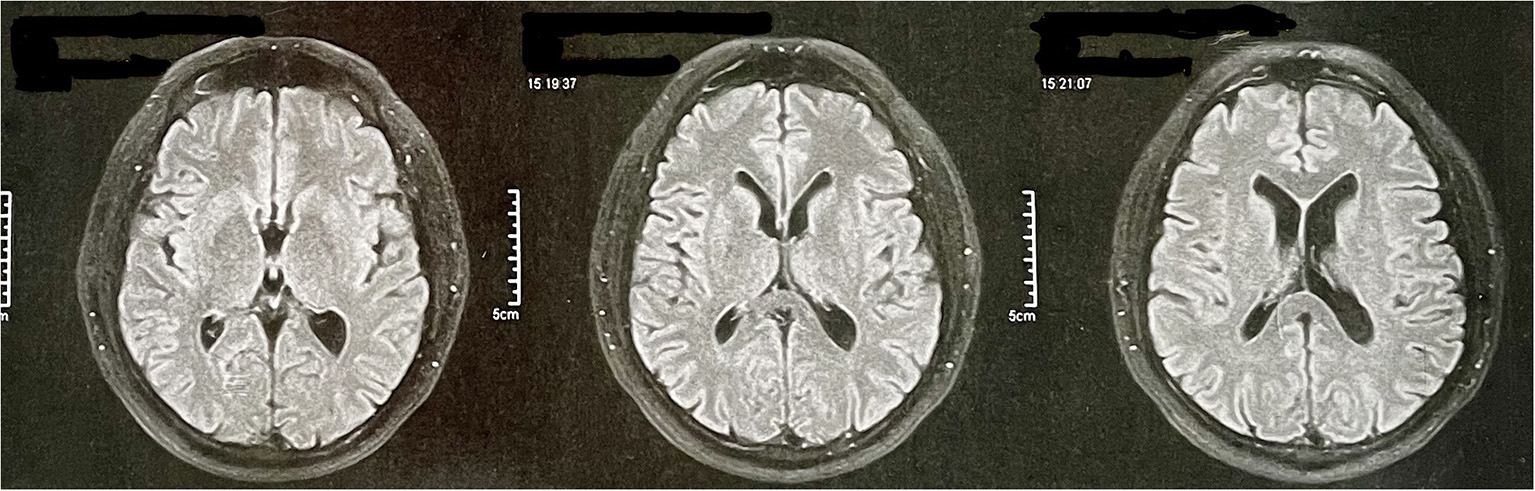

At age 56, he underwent a magnetic resonance angiography at the request of his psychiatrist. The magnetic resonance images are restricted to the T2 fluid-attenuated inversion recovery (FLAIR) sequence and only axial because they are derived from an angiographic resonance. The exam did not reveal any abnormalities (Figure 2). At this time, he was still under treatment for behavioral changes and was taking olanzapine and venlafaxine as pharmacological treatment. PET-CT examination was requested, but the patient does not have socioeconomic conditions to perform it.

Figure 2. Patient's magnetic resonance angiography data. The magnetic resonance images are restricted to the T2 FLAIR sequence and only axial because they are derived from an angiographic resonance.

Initially, the behavioral variant of frontotemporal dementia (bvFTD) was considered, as it is a common cause of young-onset dementia. In addition, it has relevant characteristics related to behavioral and personality changes (23, 24). Yet, in addition to not meeting the minimum criteria established by the International Behavioral Variant FTD Criteria Consortium (25), the patient had severe impairments in cognitive domains—such as memory and spatial disorientation—from the beginning, which are considered exclusion criteria for bvFTD (24). The speech alterations presented by the patient during the evaluation also stood out, leading to an investigation of the linguistic variants of FTD. As the neuropsychological results did not identify significant losses in the domain of language, and as the cognitive and behavioral changes were very prominent from the beginning—and being this is a less intense characteristic in the linguistic variants of FTD—we discard this possibility. Finally, FTD was discarded because the image examination does not indicate any type of cortical atrophy (Figure 2).